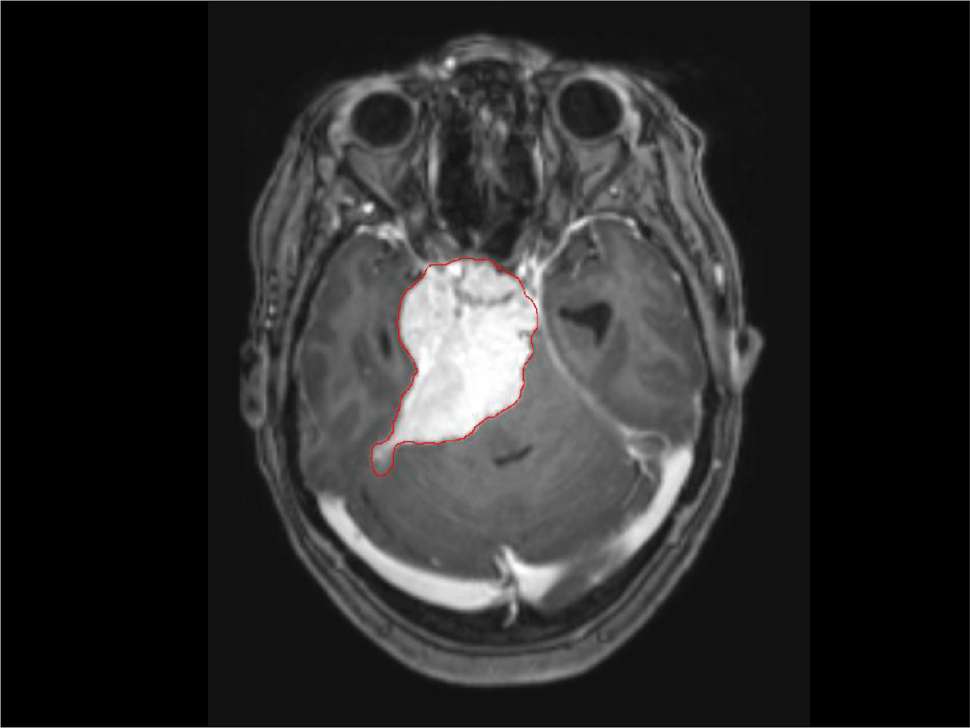

An MRI of a brain with meningioma. The meningioma is identified with a red outline.

In a study of childhood cancer survivors, researchers in the Radiation Epidemiology Branch (REB), observed that children who received radiotherapy had an increased risk of developing meningioma, cancer of the membranes that surround the brain and spinal cord (meninges). This study was published in JAMA Oncology on October 6, 2022.